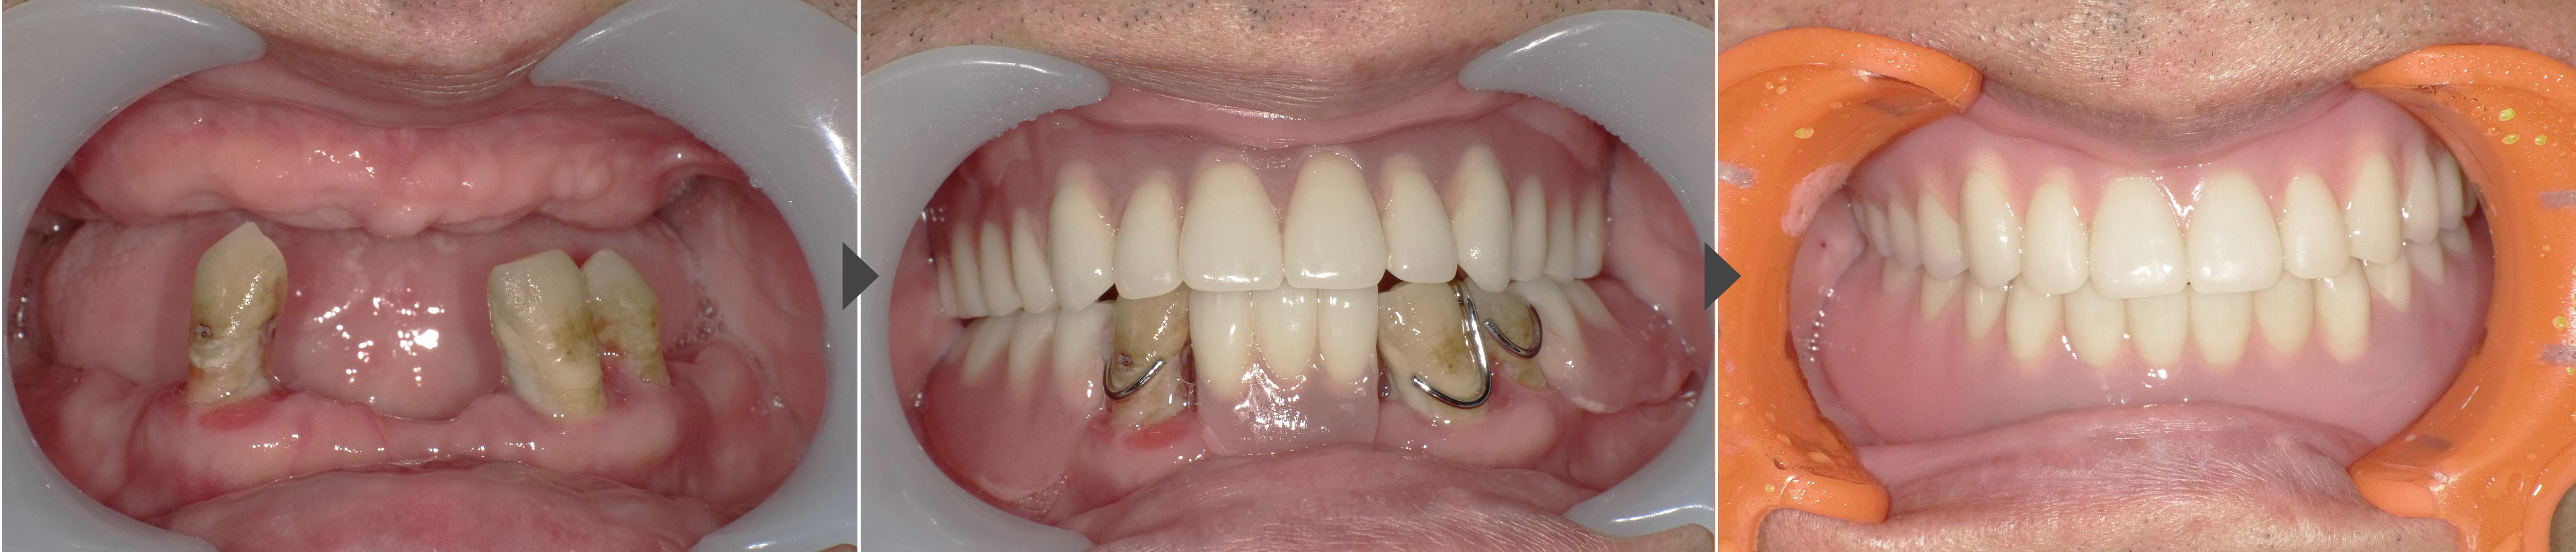

患者様は、下あごに3本の歯が残っていましたが、ぐらつきが強く、しっかり噛むことができない状態でした。

上あごはすでに総入れ歯を使用されており、「入れ歯が浮いて外れる」「噛みづらい」「もっと安定した入れ歯にしたい」というお悩みをお持ちでした。

噛み合わせ(顎の位置)を安定させるため、まず治療用の仮入れ歯を作りました。この仮入れ歯を使って咬み合わせの高さや口元のバランスを確認し、手術の際もこの顎位を維持できるよう準備しました。

そのうえで、手術当日に残っている歯を抜歯し、同じ日にインプラントを2本埋め込み、ロケーター(金具)を装着して入れ歯を固定する「即時荷重」を行いました。

これにより、手術当日から入れ歯を使用しながら生活ができるようにしました。

③ ロケーター装着・即時荷重

手術当日にロケーターアバットメントを取り付け、治療用義歯を内側から調整。その場でインプラントに適合させることで、当日からしっかり噛める状態を確保しました。

3か月ほど経過を観察し、インプラントが骨と安定的に結合したことを確認。その後、見た目・咬み合わせ・発音などをさらに整えた最終のロケーターデンチャーを作りました。

今回の症例では、治療用義歯であごの位置を安定させたうえで、抜歯と同時にインプラントを埋め込み、ロケーターを即時装着しました。

手術当日から入れ歯を使えるようにすることで、見た目や咬み合わせを保ちながら、早期に快適な咀嚼機能を回復できました。「入れ歯が合わない」「動いて痛い」「インプラント固定式までは望まない」という方に、ロケーターデンチャーは現実的で安心できる選択肢です。